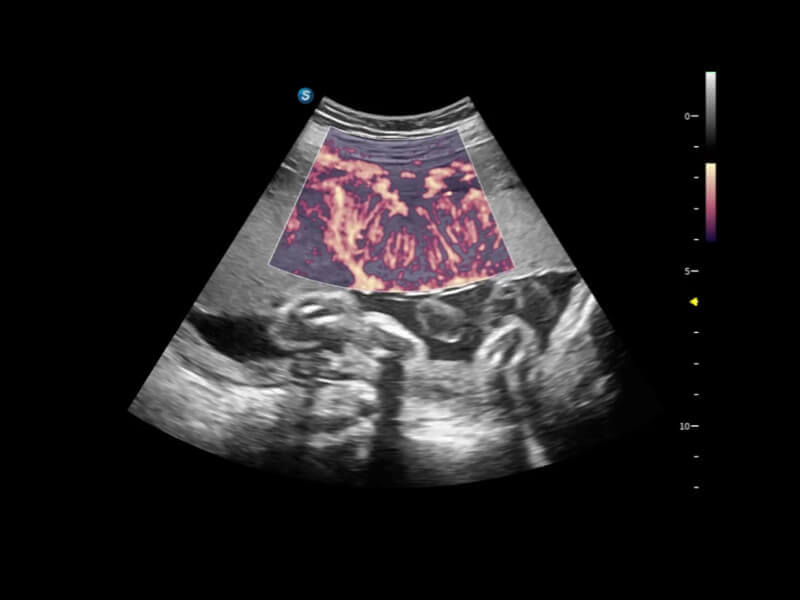

Fein abgestimmte hämodynamische Lösung

Eine Vielzahl hämodynamischer Diagnosetechniken ermöglicht eine effektive Blutflusssignaldetektion in verschiedenen Szenarien.

• FHR

FHR ermöglicht die Beobachtung der mikrovaskulären Struktur in Organen mit erhöhter Empfindlichkeit und verbesserter Auflösung, um die Präzision bei der Darstellung des tatsächlichen Zustands der Blutzirkulation sicherzustellen.